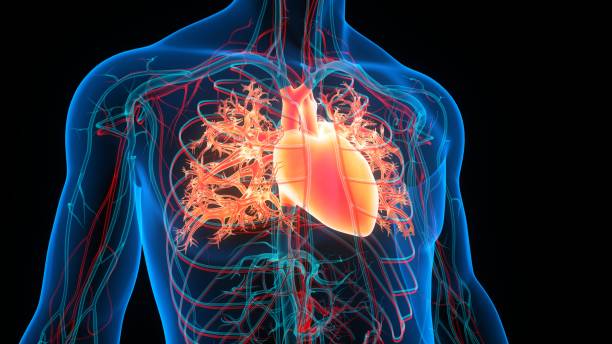

협심증은 심장의 혈액 공급이 감소하여 심장 근육에 산소와 영양분 공급이 충분하지 않아 발생하는 증상입니다. 이는 일반적으로 심장 동맥의 협착으로 인해 발생합니다. 이번 시간에는 협심증에 대해 보다 자세히 알고 초기 대응이 중요한 협심증이기 때문에 협심증의 초기 증상에 대해 자세히 정리해보도록 하겠습니다.

협심증은 심장 질환의 일종으로, 심장 근육에 충분한 혈액 공급이 이루어지지 않아서 발생합니다. 이는 심장근육에 손상을 일으키고, 심부전, 심근경색, 심부전 등의 심각한 합병증을 유발할 수 있습니다. 따라서 협심증 초기에 대응하지 않으면, 심장근육에 손상을 일으키고 이로 인해 심각한 합병증이 발생할 가능성이 높아집니다.